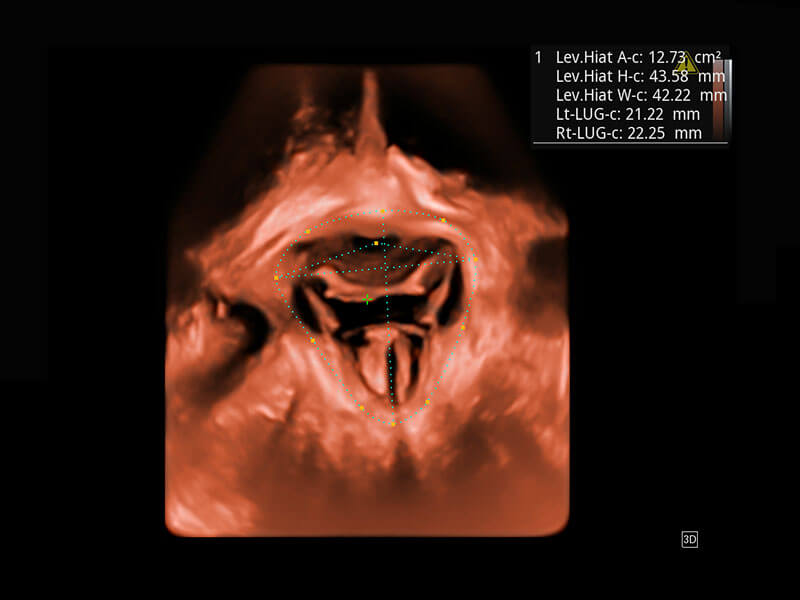

腔内三维-宫内节育器

腔内三维-光影成像

P60为盆底超声检查提供应用方案,多种腔内及腹部容积探头提供从二维、三维到四维的优异图像品质,实时快速三维容积数据获取,专业的测量工具包等人性化设计,为超声医生诊断提供有力保障。

Lev.Hiat A-r: 16.33 cm2

Lev.Hiat H-r: 53.70 mm

Lev.Hiat W-r: 43.96 mm

Lt-LUG-r: 24.16 mm

Rt-LUG-r: 19.94 mm

能够简化盆底检查的操作流程,可在二维模式及三维成像模式下实现一键自动提取出标准切面、自动识别当前切面、自动测量,提升盆底检查的高效性,同时也能让青年医生快捷的获得准确的检查结果。